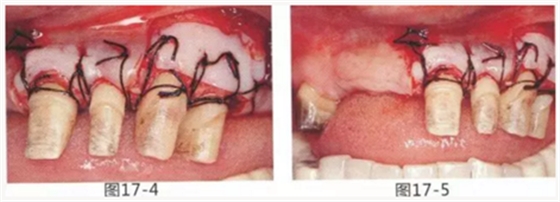

為了在左上1,2,3,4部位增加附著齦,左上1,2部位用Apically Positioned Flap(齦瓣根尖側(cè)轉(zhuǎn)移),左上3,4部位用游離齦移植的病例

圖17-1~3 左上3的牙周袋探測(cè)值為3mm,角化牙齦寬度為2mm。也就是完全不存在附著齦,如果這種狀態(tài)下佩戴修復(fù)體的話,很有可能發(fā)生頸部暴露等問(wèn)題。

圖17-4 左上1,2進(jìn)行齦瓣根尖側(cè)轉(zhuǎn)移,左上3,4進(jìn)行游離牙齦移植,在去除牙周袋的同時(shí)獲取附著齦。

圖17-5 牙周治療完成后的正面照。左上3,4部位處游離齦移植片的上端通過(guò)骨膜縫合固定在頰側(cè)嵴頂部。這樣可以使其愈合效果與齦瓣根尖側(cè)轉(zhuǎn)移相同。